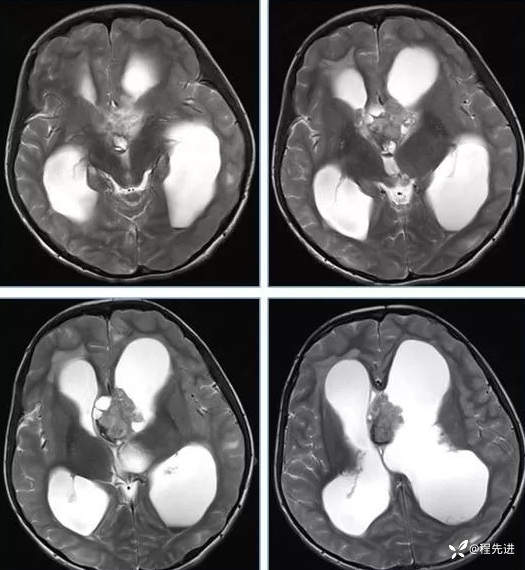

【神经】特别精彩病例|行走不稳2月余

患者性别:男

患者年龄:13岁

主诉:行走不稳2月余

现病史:2个月前患者无明显诱因下出现行走不稳,近期症状逐渐加重,站立不能。病程中患者无意识障碍,无头痛头晕,无明显恶心呕吐、视物旋转、耳鸣、眼球活动障碍等,无尿量增多、泌乳、口干等,体重无明显改变,睡眠可,食欲可,二便正常。

专科检查:右侧肢体肌力III-IV级,左侧肢体肌力IV级,肌张力下降